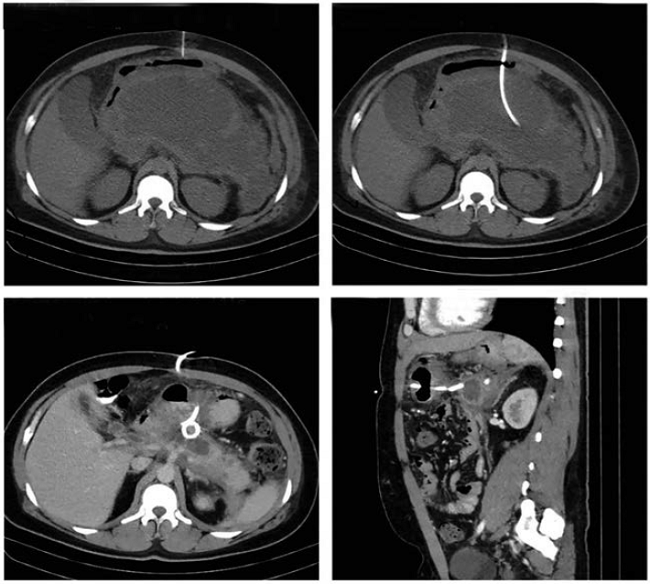

Los pacientes que tenían laparotomías previas para el tratamiento de complicaciones de pancreatitis aguda grave, fueron los que necesitaron mayor número de drenajes percutáneos para su resolución. La colocación de endoprótesis (stent) doble J transgástrica percutánea, fue una opción terapéutica efectiva en el caso de catéteres transgástricos con drenaje persistente de líquido pancreático, en los casos de fístula pancreática. El lavado continuo con solución salina a través de los catéteres en el caso de la necrosis pancreática infectada, permitió el lavado del lecho pancreático, así como la obtención de fragmentos de necrosis a través de los catéteres (figuras 1 y 2).

Con relación a la técnica, la mayoría de las intervenciones (86,6 %) fueron procedimientos de tipo Seldinger guiados por ecografía (66 %) y una menor proporción por TC (34 %). Las vías de acceso fueron transperitoneal (86,6 %), transgástrica (10,4 %) y transglútea (2,8 %), según la ubicación de la colección (figuras 1,2,3,4,5). La duración media del acto quirúrgico fue de 48,7 minutos (desviación estándar de 19,9 minutos). Los catéteres más utilizados fueron el 10 FR y el 8 FR, 37 % y 35 %, respectivamente; y el 64 % de las veces el catéter se mantuvo menos de 10 días. La mayor parte del material drenado fue de tipo purulento (64,2 %) con volúmenes que oscilaron entre 10 y 2.000 ml.

Además de los pacientes con abscesos hepáticos y colecciones posquirúrgicas, aquellos con complicaciones por pancreatitis aguda, incluida la necrosis pancreática infectada, también se beneficiaron del drenaje percutáneo guiado por imágenes. La colocación de la endoprótesis (stent) doble J transgástrica percutánea, fue una opción terapéutica efectiva en el caso de catéteres transgástricos con drenaje persistente de líquido pancreático por fístula pancreática. Esta opción permite el drenaje del líquido pancreático hacia el estómago, sin recidiva de colecciones en el retroperitoneo.